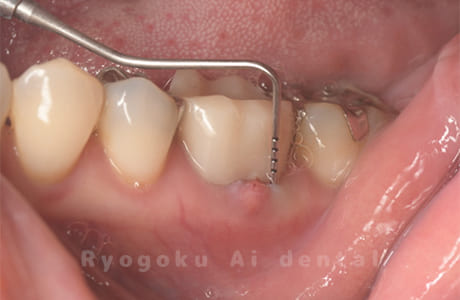

Case03

-

- 原因

- 歯牙破折

- 治療内容

- MTA治療

- 治療費用

- ¥55,000

右下の奥の歯が割れているとのことで他院で抜歯を宣告され、保存希望で当医院来院された患者様です。歯周ポケットもなくなり、現在、問題なく経過しており、患者様も満足されております。

<リスク・副作用>

手術後は痛み、腫れ、痺れ、青あざなどの副作用が生じます。痛みは痛み止めを処方しますが、腫れ、青あざは1週間程度生じる場合があります。また、部位によっては神経の走行が複雑で、痺れが残り、長期的にお薬を処方する場合があります。